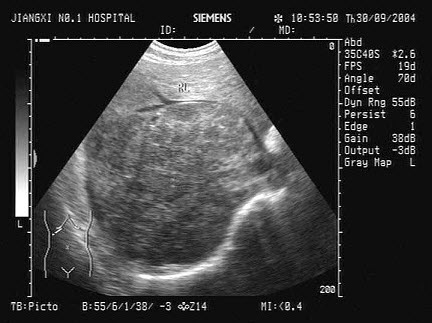

12、单项选择题

男,60岁,上腹疼痛不适数10年。结合超声声像图,诊断为()

A.胆囊多发性结石

B.胆囊多发性息肉

C.胆囊泥沙样结石

D.胆囊充满性结石并萎缩性胆囊炎

E.胆囊胆固醇结晶